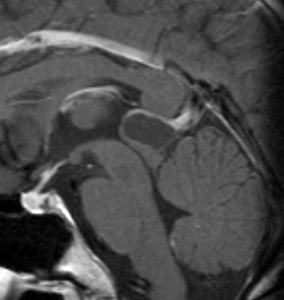

これも成人女性に偶然見つかった松果のう胞です。少し大きめですが,何も治療する必要はありません。中脳水道という所が狭くなっていますが,はっきり閉塞するまでは治療はしません。左がT1強調画像で黒っぽく見えます。右はT2強調画像で白く映っています。